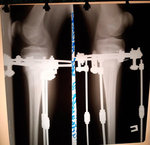

Исходник - 10 лет. Ашхабад.

Дианоз: Варусная деформация обеих оленей. Ротация с обеих сторон 35 градусов. Плоскостопие тяжёлой степени. Начальное явление артроза суставов ниних конечностей.

Дата операции - 16.04.2019г.

IMG_2484-16-04-19-07-27.JPG

IMG_2496-16-04-19-07-27.JPG